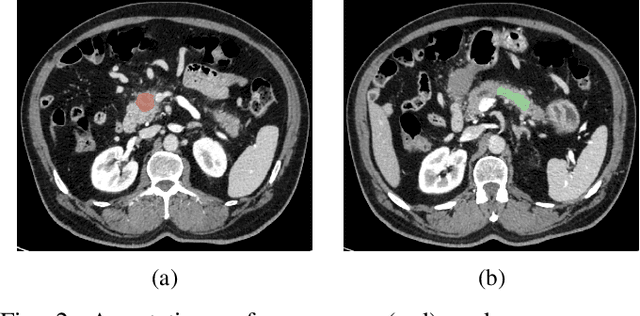

Deep Convolutional Neural Networks (CNNs) for image classification successively alternate convolutions and downsampling operations, such as pooling layers or strided convolutions, resulting in lower resolution features the deeper the network gets. These downsampling operations save computational resources and provide some translational invariance as well as a bigger receptive field at the next layers. However, an inherent side-effect of this is that high-level features, produced at the deep end of the network, are always captured in low resolution feature maps. The inverse is also true, as shallow layers always contain small scale features. In biomedical image analysis engineers are often tasked with classifying very small image patches which carry only a limited amount of information. By their nature, these patches may not even contain objects, with the classification depending instead on the detection of subtle underlying patterns with an unknown scale in the image's texture. In these cases every bit of information is valuable; thus, it is important to extract the maximum number of informative features possible. Driven by these considerations, we introduce a new CNN architecture which preserves multi-scale features from deep, intermediate, and shallow layers by utilizing skip connections along with consecutive contractions and expansions of the feature maps. Using a dataset of very low resolution patches from Pancreatic Ductal Adenocarcinoma (PDAC) CT scans we demonstrate that our network can outperform current state of the art models.